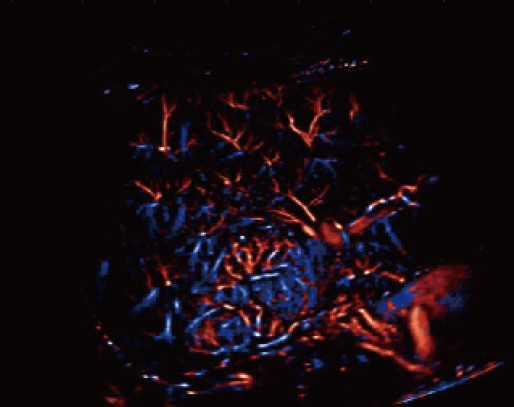

Grazie alla piattaforma AIT, Resona A20 offre una soluzione integrata completa per l'imaging a super-risoluzione, una capacità finora difficile da raggiungere. La SR CEUS rivela i dettagli intricati del microcircolo delle lesioni a livello di micron, favorendo gli studi di perfusione microcircolatoria in oncologia.

Risoluzione a livello di micron

Capacità di rilevamento microvascolare

Strumenti di quantificazione

Iperplasia nodulare focale

Iperplasia nodulare focale | Mappa densità

Mappa della densità del flusso sanguigno con iperplasia nodulare focale

Iperplasia nodulare focale | Mappa direzione

Iperplasia nodulare focale | Mappa velocità